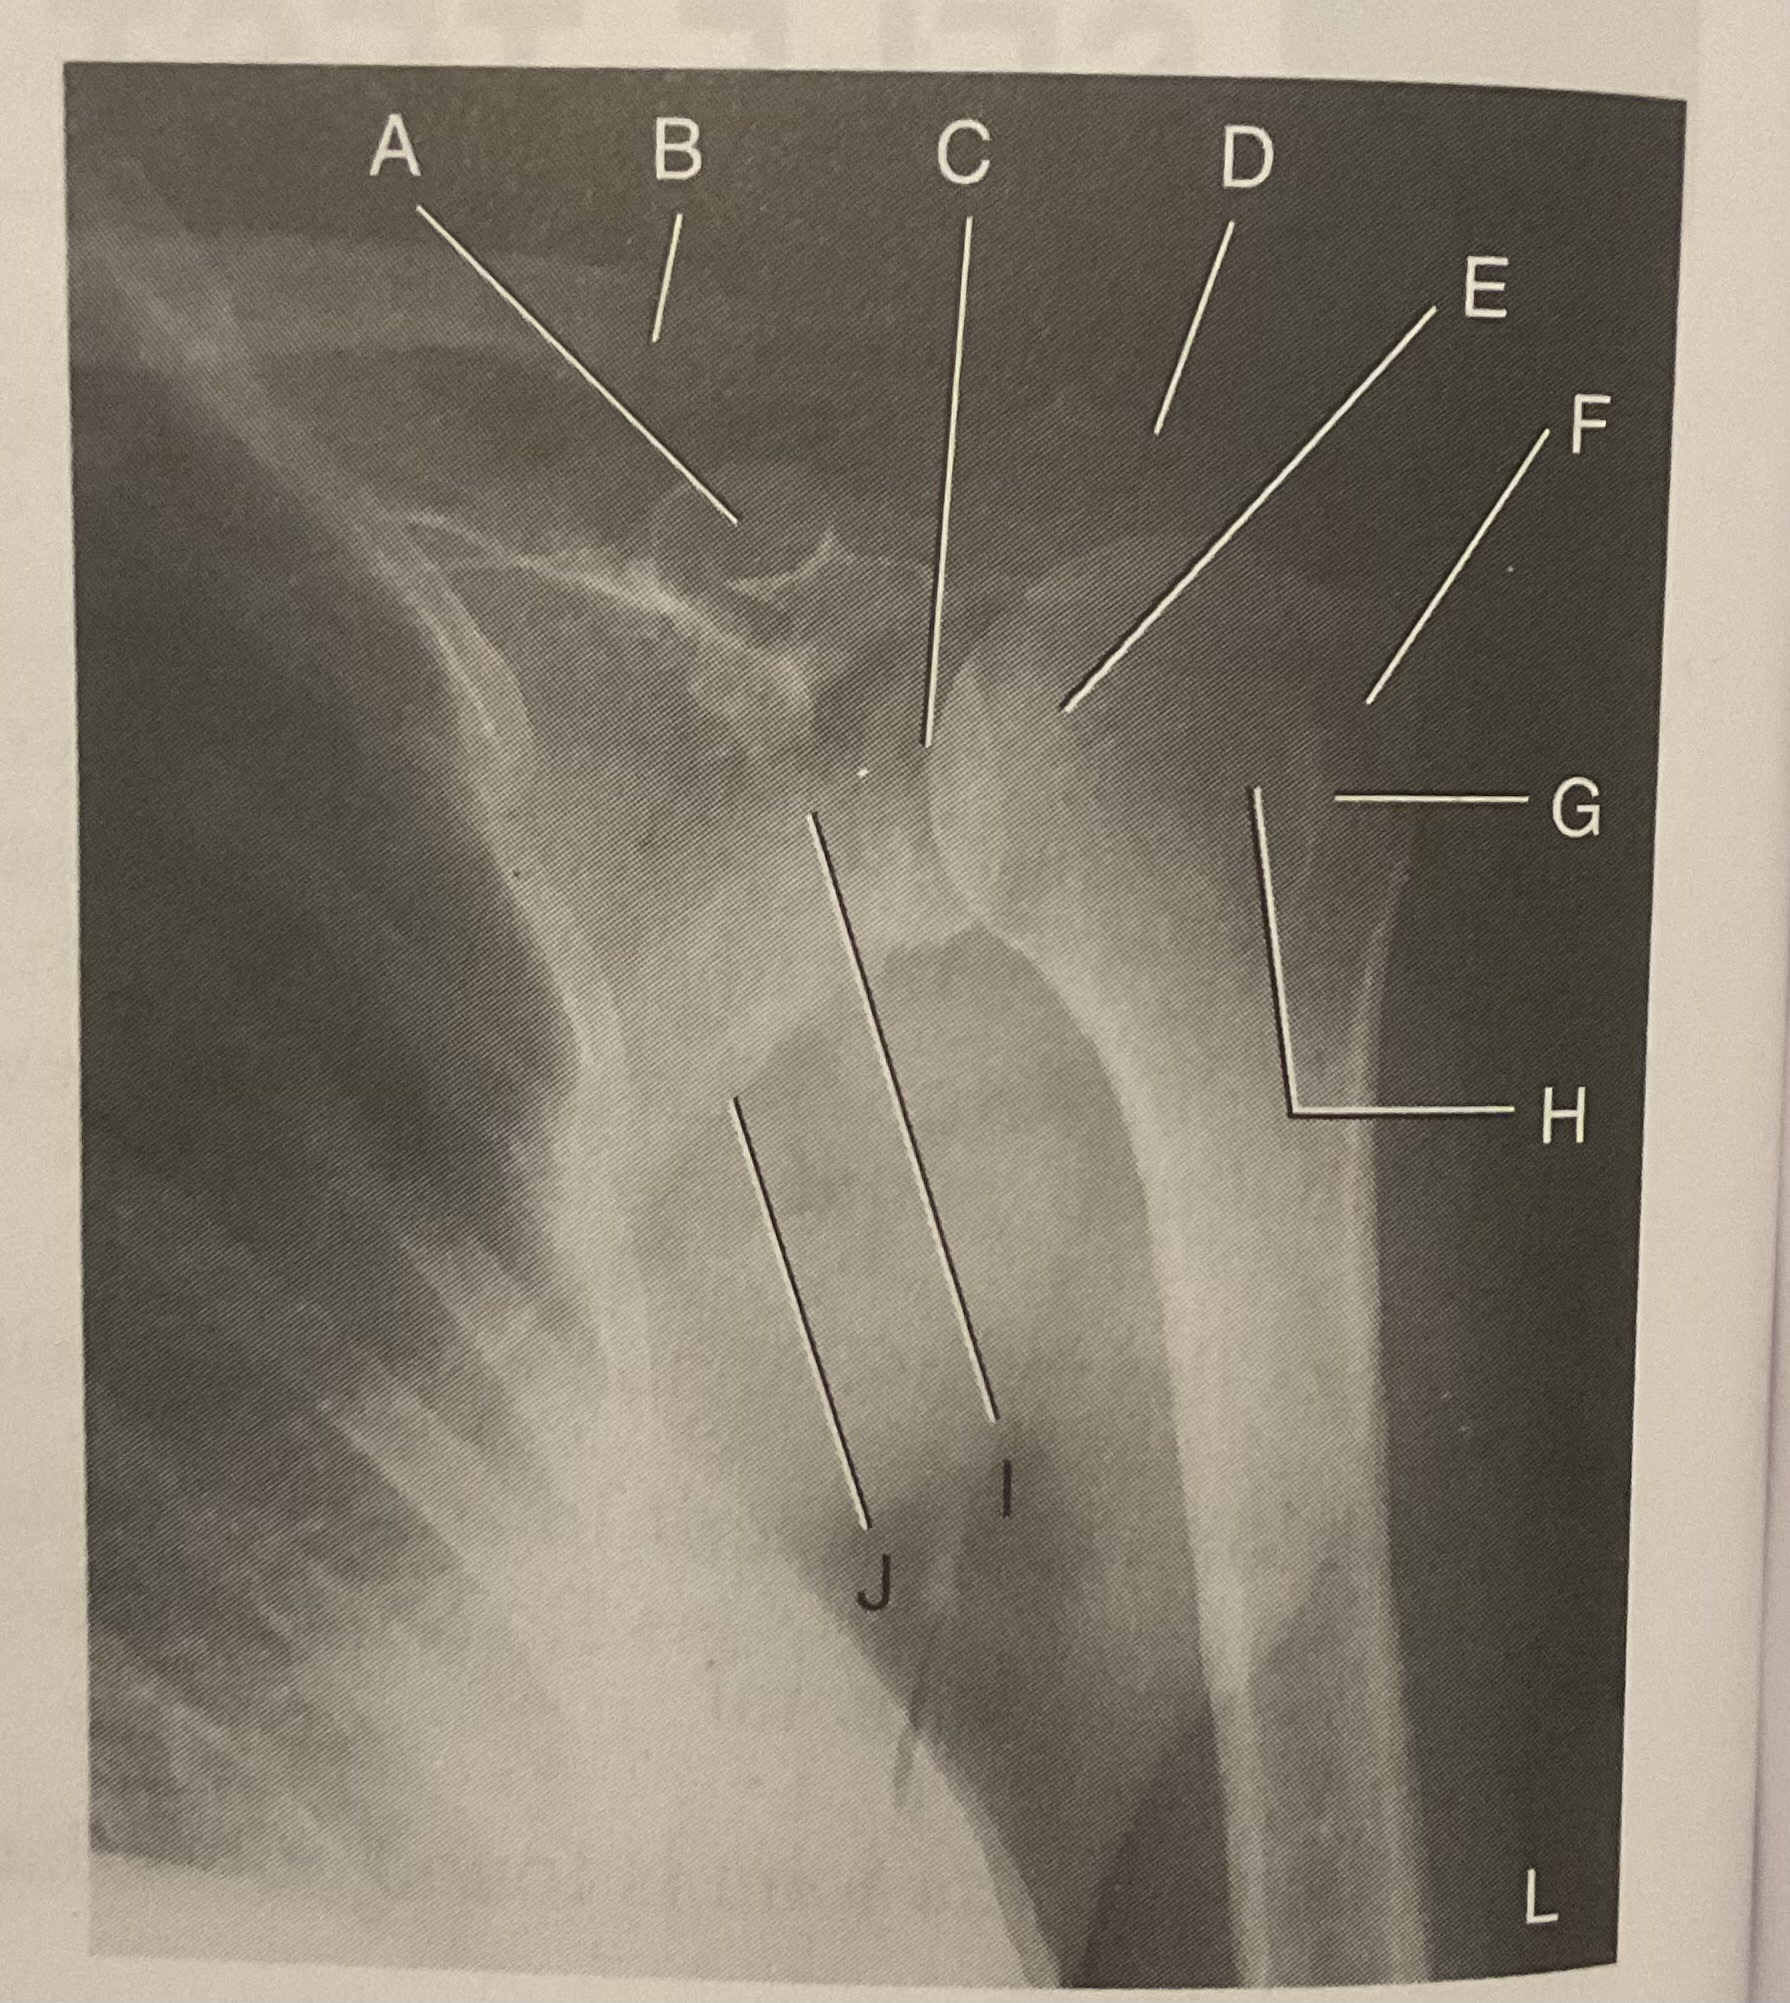

A?

Coracoid process

B?

Clavicle

C?

Scapulohumeral joint

D?

Acromion of scapula

E?

Head of humerus

F?

Greater tubercle

G?

Intertubercular sulcus

H?

Lesser tubercle

I?

Neck of scapula

J?

Lateral (axillary) border of scapula

What AP projection does this image represent?

External